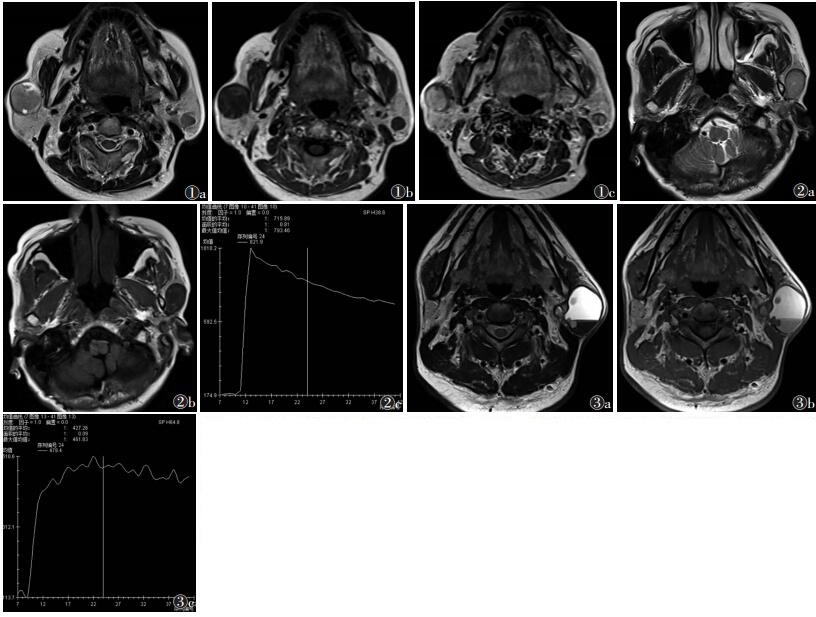

2 结果 2.1 病灶部位及一般特点11例共12个病灶,10例单发,1例左右侧各1个(图 1)。左侧8个,右侧4个。8个位于腮腺浅叶,4个位于跨腮腺深浅叶。病灶长径1.0~5.0 cm,平均2.53 cm。11个边界清楚、光滑。9个呈圆形或卵圆形,3个出现浅分叶。12个边缘均见线状长T1短T2信号包膜,11个病灶包膜完整;1个病灶边界不清,包膜不完整,术前误诊为恶性肿瘤。

| 图 1 女,83岁,双侧腮腺基底细胞腺瘤(BCA) 图 1a 横轴位T2WI,肿瘤呈中等稍高信号,右侧病灶内外周见小片囊变高信号 图 1b 横轴位T1WI,病灶呈低信号 图 1c 横轴位增强T1WI,病灶明显强化 图 2 女,59岁,左侧腮腺BCA 图 2a T2WI病灶呈中等稍高信号 图 2b T1WI病灶呈低信号 图 2c DCE-MRI病灶强化模式为速升速降,TIC呈B型 图 3 男,49岁,左侧腮腺BCA 图 3a T2WI肿瘤大片囊变呈高信号,出血呈低信号,内部呈液-液平,边缘壁结节向腔内隆起,周围见线状低信号完整包膜 图 3b T1WI囊变、含黏液呈高信号,出血呈中等稍高信号 图 3c DCE-MRI示壁结节强化明显,TIC为平台型 |

病灶与同层面肌肉相比,呈等T1稍长T2信号,但均低于正常腮腺信号,以实性病灶为主(图 2)。病灶一般情况、ADC值、TIC、病理类型见表 1。8个出现大小不等囊变区,3个囊变区内见短T1短T2信号,出血并形成液-液平面并可见壁结节(图 3)。DWI高b值图呈稍高信号,12个病灶ADC值(0.945~1.285)×10-3 mm2/s,平均(1.121±0.189)×10-3 mm2/s。